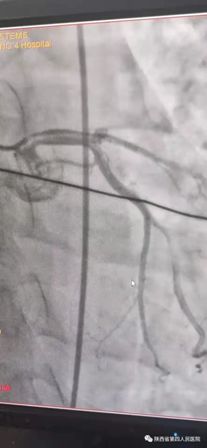

11月10日15时58分左右,家住21点基本策略 附近的中年男性辛先生在家人陪伴下来到我院急诊内科门诊诊室,满头大汗,捂着胸口说胸痛、胸闷、气短,急诊科主治医师钟高亮立即安排床位进行留观给予吸氧、心电监护、查体,心电图提示:1、窦性心律;2、室性早搏;3、急性下壁、前壁心肌梗死,诊断:急性冠脉综合征、心肌梗死。随后患者在急诊科留观室病情突然加重,意识丧失、四肢抽搐、面色苍白、全身大汗、呼吸急促,心电监护提示心室颤动,判断其可能为急性心肌梗死心源性休克,急诊科和心内科医生立即行胸外心脏按压,电除颤三次等对症治疗,立即启动胸痛患者抢救应急预案,开启绿色通道,和患者家属谈话,为其迅速办理入院手续,给予升压补液扩容等抢救治疗,积极完善术前准备,联系医务科和介入导管室,于16时22分将患者转运至导管室,心内科主任、主任医师王选琦带领团队副主任医师孙耀林、王崇振,主治医师马艳萍共同夺取患者最宝贵生命时间,为患者选择了从下肢股动脉穿刺造影,从穿刺到开通血管用仅仅只用了十一分钟。16时33分顺利完成PAG PCI支架植入术后成功再通,患者转危为安,随后入住心血管内科CCU病房继续治疗。

(术前造影) (术后)